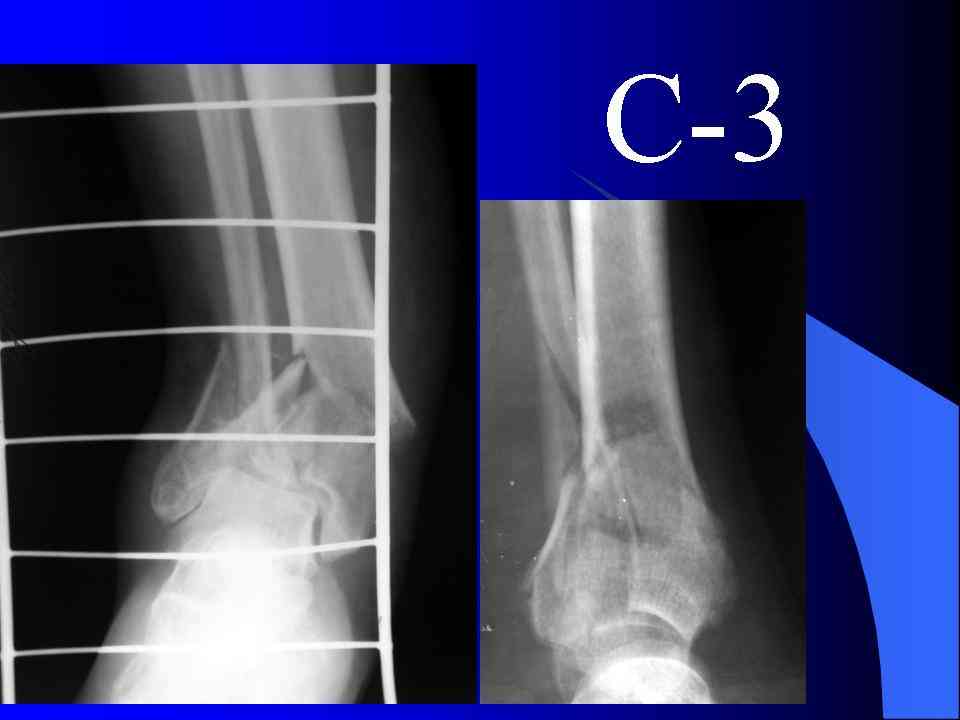

Кстати, при переломах переднего края по классификации АО В-3 при переломах пилона пластина укладывается по передней поверхности. Она достаточно тонкая и эластичная, не надо этого бояться. Посылаю три снимка.

На рентгенограммах типичный перелом пилона по типу С-3. есть опыт до 100 открытых опреаций у нас в клинике. 20 примерно в год. Принцип один -все внутрисуставные переломы нуждаются в открытой репозиции и внутренней стабильной фиксации. При поступлении КТ не надо, так как получается только нагромождение костей. Истинной картины нет. Главное восстановить длину малоберцовой кости - это ключ к успеху. При поступлении меньше всего надо думать о сосудистых расстройствах, т.к. сама операция и репозиция даже сначала частичная даёт улучшение сосудитых нарушений. Причём очень быстро. Операция в 2этапа. При поступлении доступ позади наружной лодыжки, причём обязательно. После этого репозиция малоберцовой кости и фиксация пластиной 1/3 трубки под винт 3,5. Дренаж и любой аппарат наружной фиксации. Затем после спадения отёка на 5-7-10 день аппрат снимается и дугообразный разрез спереди от медиальной лодыжки 10-12 см. Главной чтобы расстояние между 1 и вторым разрезом было не меньше 7-8 см. Тогда не будет некрозов лоскутов. Таранная кость используется как матрица на неё укладываются отломки и фиксируются пицами. Ренг-контроль. Отломки лежат все отдельно, но ничего не высыпется. При переломах С-3 всегда нужна костная пластика (из крыла). Фиксация пластиной лист клевера простой или LCP. Гипс не нужен. Дренаж до 48 часов. Операция длится 3-4 часа обязательно без жгута. Посылаю примерно такой же случай.